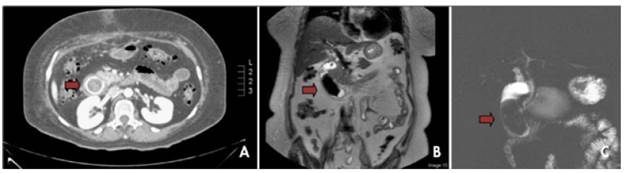

Vital signs on admission were: blood pressure of 120/80 mmHg, temperature of 38°C, oxygen saturation of 98%, pulse of 80 bpm, and respiratory rate of 19 per minute. Blood count test reported leukocytes 19.05 x103/ul; neutrophils 82.3%; 9% lymphocytes; red blood cells 3.78 M/ul; hemoglobin 10.1 g/dl; hematocrit 29.9%; platelets 626 x103/ul; bilirubin: total 0.49 mg/ dl, direct 0.21 mg/dl and indirect 0.28 mg/dl; electrolytes: sodium 147 mEq/L, potassium 3 mEq/L and chlorine 99 mEq/L; gamma glutamyl transferase 120 M/L; alkaline phosphatase 107 U/L; Amylase 102 U/L; lipase 142 U/L, and PCR 47.69 mg/L. After the tests were performed, imaging was requested, revealing the presence of the large gallstone in the second part of the duodenum (Figure 1).

A) Three-phase computed tomography of the abdomen in venous phase; B) and C): T2-weighted SPAIR magnetic resonance cholangiography.

Figure 1: A) Three-phase computed tomography of the abdomen in venous phase; B) and C): T2-weighted SPAIR magnetic resonance cholangiography.